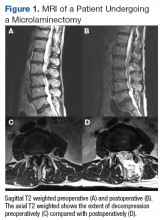

Fifty veterans with severe lumbar stenosis and neurogenic claudication underwent a 1- or 2-level laminectomy at SAVAHCS (Table). A traditional laminectomy was performed for all patients until conversion to the MIS procedure, then all subsequent patients underwent the microlaminectomy. There was 1 female patient in each group. The preoperative magnetic resonance imaging (MRI) of the patients showed severe spinal canal stenosis defined radiographically by the absence of cerebrospinal fluid signal at the affected level on MRI (Figures 1A and 2A) and clinically by the presence of neurogenic claudication.

The MISS laminectomies were performed through a small unilateral paramedian incision created 1.5 cm from the midline.1 A tubular retractor system was used, and the laminectomy was performed under microscope magnification. A laminotomy initially was completed ipsilateral to the side of the incision until the ligamentum flavum and the lateral recess of the spinal canal were identified. The tube was then aimed medially so that the base of the spinous process was identified and resected. The ligamentum flavum was dissected from the undersurface of the contralateral lamina. The contralateral lamina then was resected using a high-speed drill. Finally, the ligamentum flavum was resected, and the dura was exposed. The cranial-caudal extent of the resection was confirmed using fluoroscopy. The technique allowed for significant canal expansion (Figures 1A, B, C, and D).